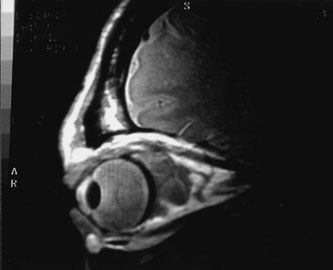

Contrast-enhanced CT of the orbits with direct and coronal cuts is the radiologic study of choice for these patients.45 A well-demarcated, encapsulated oval or rounded mass is revealed, which is typically intraconal in the lateral part of the middle third of the orbit (Fig. 5) but occasionally may extend to the extraconal space.42 Septa within the tumor may be apparent on high-resolution CT. The posterior pole of the globe frequently is indented by the rounded anterior margin of the tumor.42 The optic nerve typically is displaced rather than surrounded by the tumor. Subtle outward bowing of the lateral orbital wall or increase in orbital size may be present, consistent with a long-standing, slowly growing mass lesion.10,42 Enhancement with intravenous contrast occurs and may be homogeneous or inhomogeneous.10,45 Rarely, cavernous hemangiomas may occur as an intraosseous tumor within the orbital or facial bones.42,53–55 Although usually an isolated intraorbital lesion, multiple lesions in one orbit occurred in 8 of 164 (5%) patients of three combined large studies,10,42,45 and bilateral multiple cavernous hemangiomas also have been described.56 In contrast to patients with venous flow malformations in which phleboliths are common, phleboliths are rare in cavernous hemangiomas. Three large studies comprising 164 patients with cavernous hemangioma all reported that no calcification was detected within the tumor.10,42,45If the diagnosis is still unclear or if better definition of details and localization of the lesion is required, then MRI should be performed. Magnetic resonance imaging demonstrates nonspecific characteristics of a lesion isointense to muscle and gray matter on T1-weighted images and hyperintense on T2-weighted images (Fig. 6).57 The lesions show initial central patchy enhancement, which fills up homogeneously within 20 to 60 minutes.58 If ultrasonography is performed, B-scan ultrasonography shows a well-circumscribed mass with a sharply defined anterior acoustic border.23 A-scan ultrasonography shows high reflectivity of the echo signals resulting from the multiple blood-filled vascular channels, regular internal structure with a higher anterior and posterior spike marking the capsule, and moderate sound attenuation (angle of decrease of the echo spike within the lesion).24 Arteriography is not indicated.